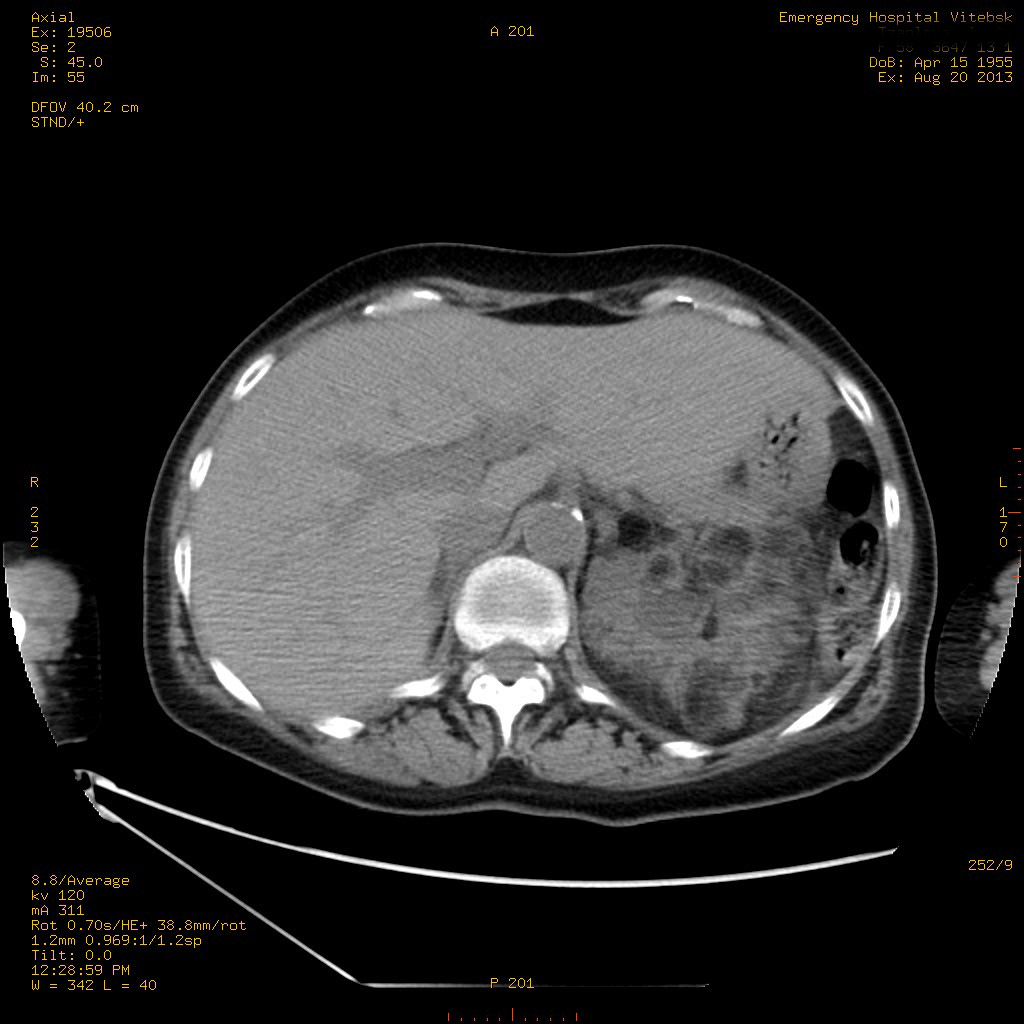

Пожилая женщина с нормальными мочевиной и креатинином.

Ангиомиолипоматоз почек , думаю компонент туберозного склероза.

Да, туберозный склероз.

Случай консультирован на кафедре радиологии Католического университета г.Лёвен (Бельгия) - зав каф. профессор Р.Оуен.